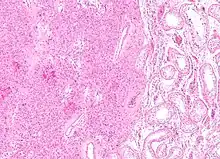

Micrograph of a granulosa cell tumour, a type of sex-cord–gonadal stromal tumour. H&E stain.

Sex cord–gonadal stromal tumour is a group of tumours derived from the stromal component of the ovary and testis, which comprises the granulosa, thecal cells and fibrocytes.[1] In contrast, the epithelial cells originate from the outer epithelial lining surrounding the gonad while the germ cell tumors arise from the precursor cells of the gametes, hence the name germ cell.[1] In humans, this group accounts for 8% of ovarian cancers and under 5% of testicular cancers. Their diagnosis is histological: only a biopsy of the tumour can make an exact diagnosis. They are often suspected of being malignant prior to operation, being solid ovarian tumours that tend to occur most commonly in post menopausal women.